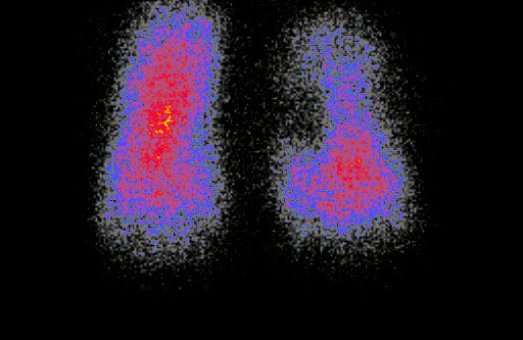

Пацієнтові вводять спеціальну речовину, в складі якої є радіонуклід, що підбирається індивідуально для певного органу чи тканини. Цей радіонуклід випромінює гамма-кванти, які фіксуються сучасною апаратурою. Важливо підкреслити: променеве навантаження при цьому у 100 разів менше, ніж при звичайному рентгені. Це робить метод безпечним навіть для ослаблених пацієнтів. У результаті лікар отримує зображення, які відображають не лише структуру органу (як при УЗД або МРТ),а й його функціонування на молекулярному рівні. Завдяки цьому патологічні процеси можна виявити на 6–9 місяців раніше, ніж іншими методами. Чим раніше встановлений діагноз — тим більше шансів на успішне лікування.

Використовуються сучасні радіонуклідні методики, що дозволяють виявити навіть приховані захворювання на початковому рівні.